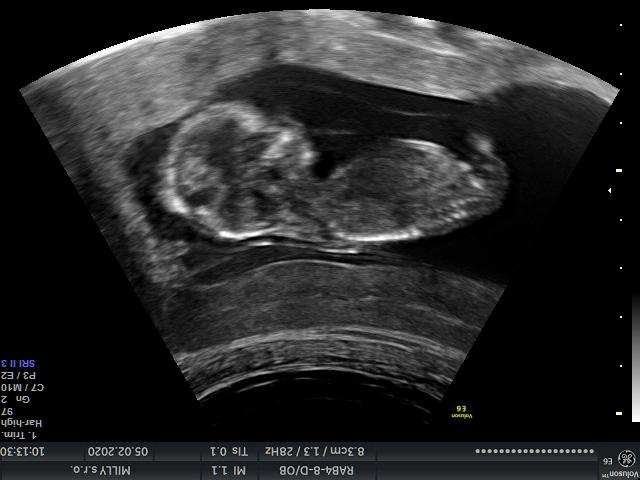

@flowerkacrochet 3D nemám, iba tvaricku. Úprimne o nič mi neide, len možno niekto z tohto obrázka prečíta viac ako ja 😄 už by som si chcela pomaly kupovať vybavicku, ale teda neviem ktorým smerom. Túto foto mám z 13 týždňa, ale teda ja ani tam pohlavie nevidím 😄

Lékař nám ve 13 tt říkal, že pravděpodobnost, že určí pohlaví správně, je v tomto týdnu těhotenství 50%.

@krupka3 ďakujem za odpoveď, ono pri prvej dcérke mi už v 13 týždni povedal, že to bude dievčatko a na každom jednom ulttrazvuku sa to iba potvrdilo. No nič, budem musieť vydržať 😄 samozrejme prvé čo ma zaujíma či je všetko v poriadku, či má ručičky, nozicky na mieste, toto je ale druhá vec ktorá ma zaujíma hneď potom 😄